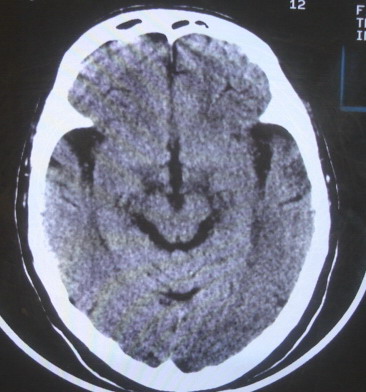

女  67岁 双下肢无力,行动不灵便

老年脑

脑萎缩,腔隙性脑梗塞.

支持老年脑改变。

脑白质病;脑委

右顶叶腔梗

双侧额桥束及左侧脑室旁多发腔梗塞+老年性脑改变

多发腔梗、老年性脑改变、脑白质异常。